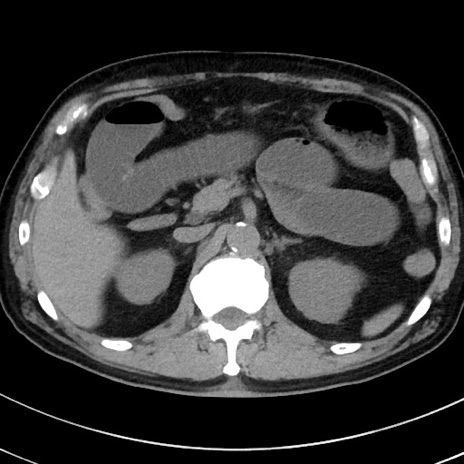

症例38(横断像)

【症例】70歳代 男性

【主訴】腹痛・嘔吐

【現病歴】昨晩より、嘔吐・腹痛あり。今朝になっても嘔吐あり。来院。

【既往歴】心臓バイパス手術、開腹胆摘、腸閉塞

【身体所見】BP 107/71mmHg、HR 116/min、腹部:平坦、軟、下腹部に軽度圧痛あり。反跳痛なし。

【データ】WBC 15100、CRP 0.32